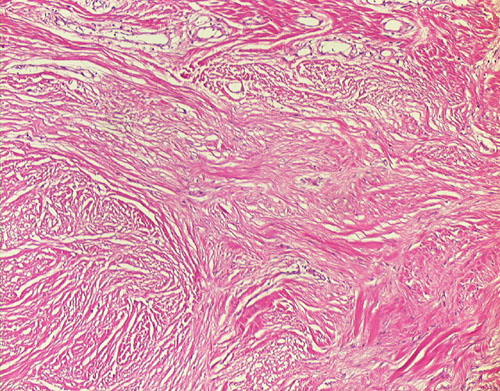

19. Fibrosarcoma

19-4.JPG (127110 bytes)19-10.JPG (125959 bytes)19-20.JPG (136926 bytes)19-40.JPG (112275 bytes)